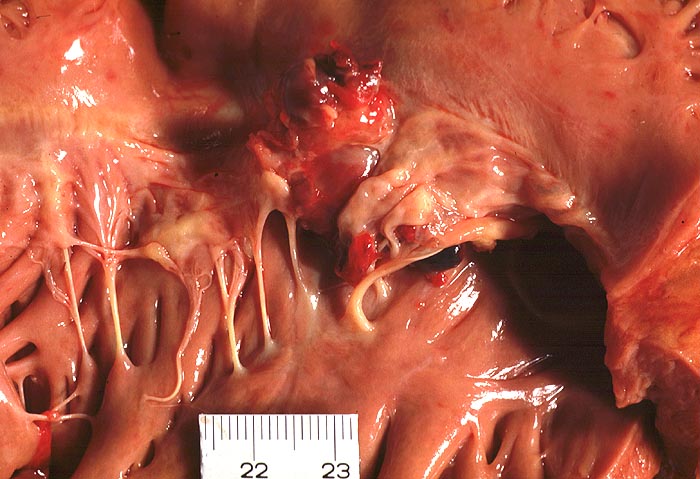

Makroskopisch sind entweder flache rötliche fibrinbelegte Ulzera (=ulcerosa (> 2935)) oder zusätzlich weiche gelbbraune bröcklige erbs- bis pflaumengrosse Polypen (=ulceropolyposa (> 2936) (> 8376)) oder ausschliesslich polypoide Fibrinbeläge (=marantica) auf einem Endokarddefekt oder einer partiell zerstörten Klappe erkennbar.

Histologisch findet sich bei ulzeropolypöser Endokarditis ein Fibrin-Thrombozytenthrombus, welcher von Bakterien durchsetzt ist (=Vegetation). Die Vegetation sitzt auf einem Klappendefekt an dessen Basis Granulationsgewebe einzusprossen beginnt, welches den Thrombus organisiert. Klappendefekte, Gefässeinsprossungen, verdickte Sehnenfäden (> 2848) oder Kommissurenverwachsungen (> 8389) der Taschenklappen weisen morphologisch auf eine abgeheilte Endokarditis hin.